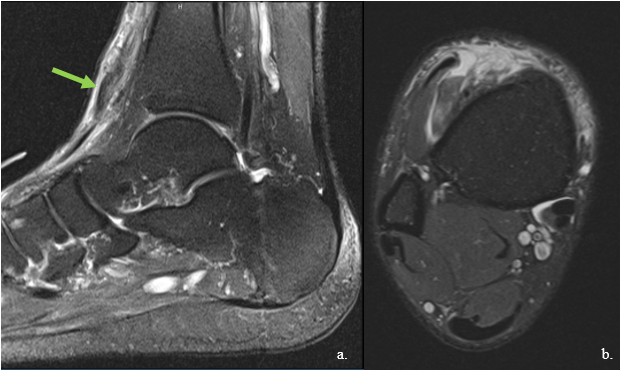

It is our common practice for the patient to initially receive weight-bearing radiographs of the foot and ankle to rule out underlying osseous involvement. Magnetic resonance imaging (MRI) of the ankle without contrast is our preferred imaging modality, especially in the chronic setting, as it is diagnostic and gives detail of the characteristics of the ruptured tendon (Click here for Figure 1).